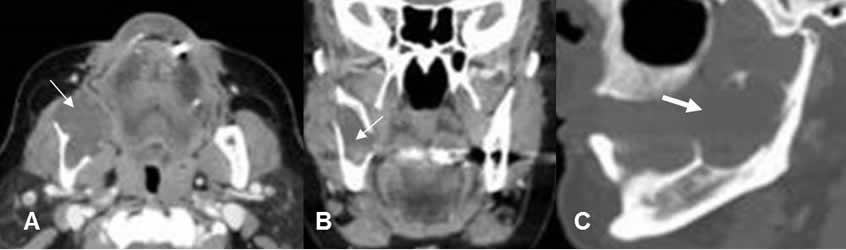

Fig 65. Ameloblastoma.

A: TAC en ventana de hueso, B: TAC axial en ventana de tejido, C: TAC reconstrucción coronal y D: TAC reconstrucción sagital. Lesión lítica y de comportamiento agresivo, que compromete la sínfisis y cuerpo de la mandíbula, con masa asociada de tejidos blandos.

Fig 66. Ameloblastoma.

A: TAC axial y B: TAC reconstrucción coronal en ventana de tejido y C: TAC reconstrucción sagital, en ventana de hueso. Masa de tejidos blandos, que expande el ángulo de la mandíbula. (Flechas delgadas). Esta lesión ocasiona ruptura de la cortical y corresponde a ameloblastoma. (Flecha gruesa).